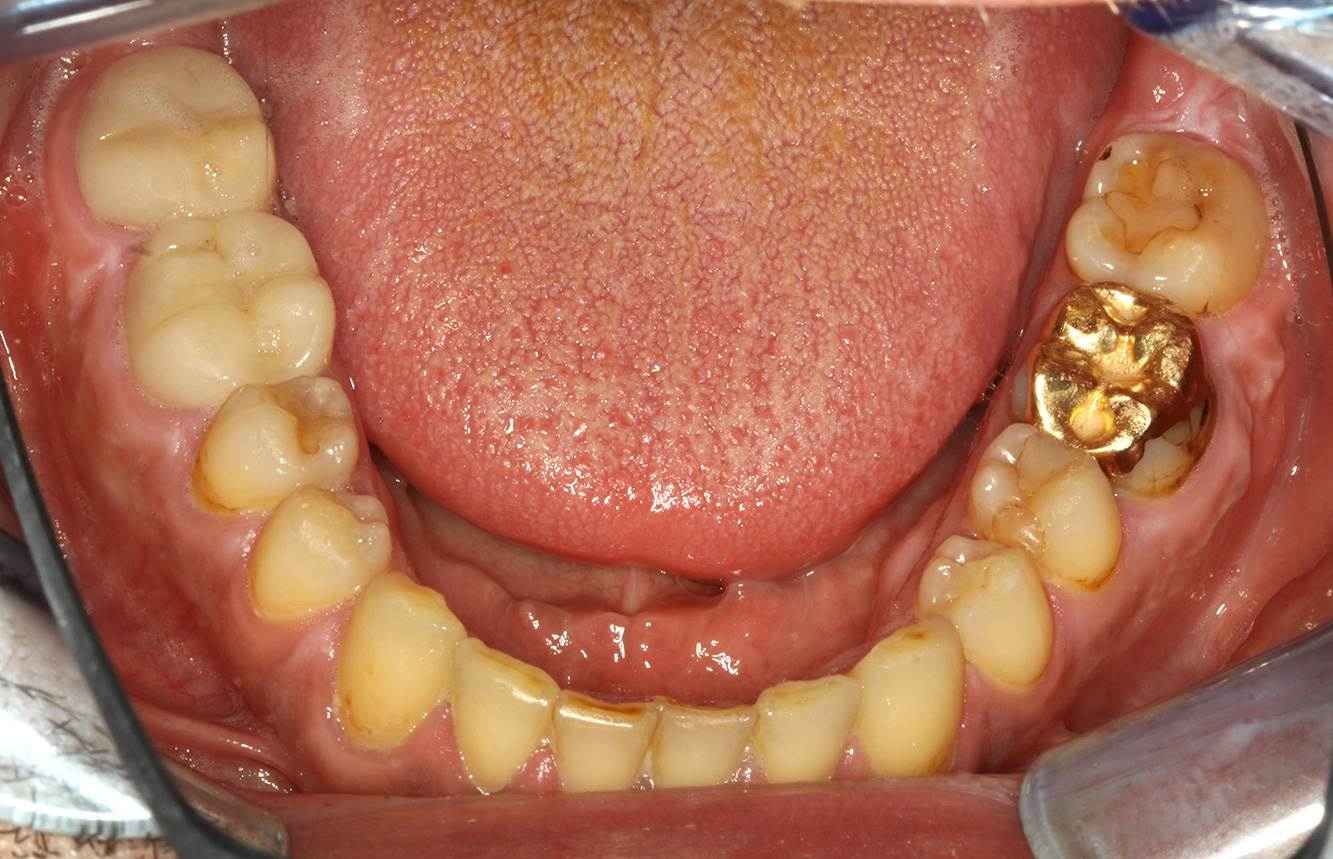

The endocarditis patient with active caries lesions*

The patient is 39 years old and has previously undergone aortic valve replacement due to valve failure and endocarditis. ASS 100 is taken regularly as an anticoagulant. In terms of lifestyle, the patient’s diet is classified as caries-promoting due to the regular consumption of sugary foods and the fact that six to seven meals are consumed daily. The patient’s oral health indicates a moderate risk of caries, with active lesions. The risk of periodontitis is low, but gingivitis is present. The following recommendations are made for prophylactic treatment.

The heart valve replacement and the history of endocarditis indicate an increased risk of complications. In order to reduce the risk of inflammation recurring, antibiotic prophylaxis is recommended (e.g. 2 g amoxicillin, 1 hour before the session). Despite the long-term blood-thinning medication, it is not expected that there will be an increased risk of bleeding in the prophylactic session.

No specific instrument recommendations can be determined for the prophylaxis session. Targeted application of air and rotary polishing can be used to gently reduce plaque and stains on the restoration edges, and to reduce recolonization niches for cariogenic bacteria (19).

Fluoridation is recommended to further support the prevention of caries, and especially to prevent new formation around the restoration edges, and to seal the root surfaces. Both of these measures can reduce the teeth’s sensitivity to temperature.

Due to the active caries lesions and the associated risk of progression, a shortened recall interval of three to four months is recommended.